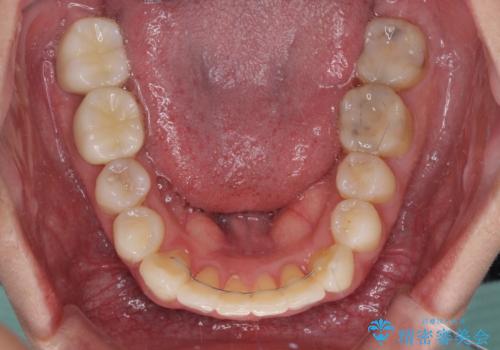

短期間で手間のかからない方法がご希望でしたので、ワイヤー装置による矯正治療を行うこととし、矯正治療後に右奥2歯をセラミッククラウンにて補綴することとしました。

セラミッククラウンによる補綴治療と矯正治療の双方が必要となる場合、矯正治療前の処置や歯の移動中に必要な処置など、二種類の治療を同時にチェックすることがとても重要となります。

当法人では、1つの医院で全ての診療を進めることができるため、このような方には大変お勧めです。